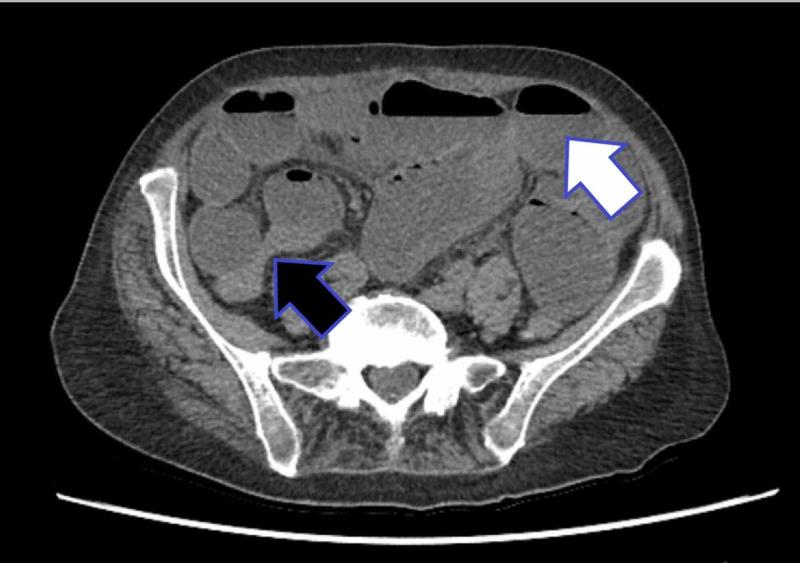

Gallstone ileus is a rare but significant cause of bowel obstruction. An 82-year-old female was admitted to the hospital with abdominal pain and was initially treated for a possible urinary tract infection. Following a surgical review and based on history, clinical examination as well as radiological findings, a diagnosis of gallstone ileus was made. The patient was prepared for surgery; however, whilst awaiting theatre, she spontaneously passed the obstructing gallstone with full resolution of bowel obstruction symptoms. The usual treatment for gallstone ileus is surgical management with an enterolithotomy; nevertheless, this case highlights the importance of close monitoring and adapting a management plan to fit an evolving clinical scenario.

胆石性肠梗阻是一种罕见但重要的肠梗阻病因。一名82岁女性因腹痛入院,最初因可能的尿路感染接受治疗。经过外科会诊,并根据病史、临床检查以及影像学检查结果,诊断为胆石性肠梗阻。患者已做好手术准备;然而,在等待手术期间,她自行排出了阻塞性胆结石,肠梗阻症状完全缓解。胆石性肠梗阻的常规治疗方法是行肠石切除术;尽管如此,该病例凸显了密切监测以及根据不断变化的临床情况调整治疗方案的重要性。